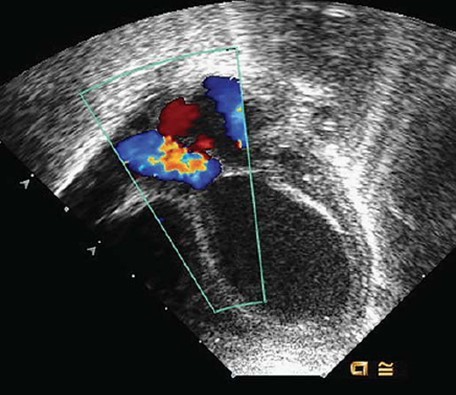

Chapter 4: The Genetics of Abnormal Cardiac Development in Pediatric Practice: Cardiology highlights the genetic underpinnings of CHDs. However, it also recognizes that most causes of CHDs are unknown, as shown in Figure 4-1 (top). Other known factors to contribute to the development of CHDs are illustrated in Table 4-1 (bottom).

Figure 4-1: Gleason M, Rychik J, Shaddy R. Pediatric Practice: Cardiology; 2012.